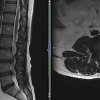

Cauda Equina Syndrome

54 Male presented with 1 week history of low back pain B/L leg pain, worse (L). Reports left leg feels heavy. 7 days ago spoke to GP regarding right leg pain. Reported that the pain had been present for 6 days. GP prescribed codeine 15mg. 3 days later called 111. Was advised to visit A&E. A&E Visit Patient has a history of paranoid [...] Read more